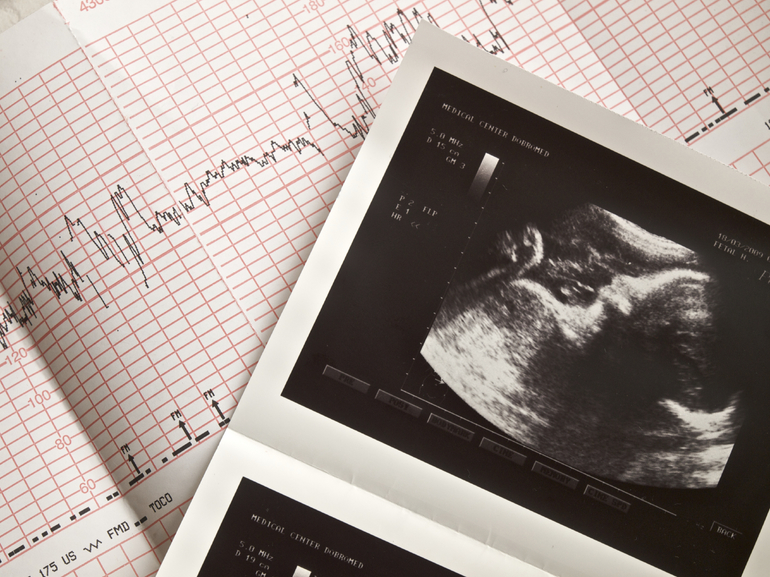

- С помощью УЗИ можно прослушать сердечный ритм эмбриона на 4−5 неделе. Если на этом сроке врач не услышал биение, возможно, оно появится позже. При повторном обследовании отсутствие сердцебиения может указывать на замершую беременность, которая требует медикаментозного прерывания. Повторная беременность рекомендуется только через полгода.

- Кардиография (КТГ) позволяет не только узнать частоту сердцебиения, но и выявить кислородное голодание плода. При обнаружении патологий можно своевременно оказать помощь. Аппарат оснащен датчиками, фиксирующими сокращения матки и движения плода, а также основными датчиками, которые записывают сигналы от сердца на пленку. Процедура занимает около 60 минут и проводится на 32-й неделе и перед родами, а в течение всей беременности — только по показаниям. Этот метод безопасен как для матери, так и для ребенка, поэтому его можно проводить столько раз, сколько необходимо. Если пульс плода составляет 120−160 ударов в минуту и увеличивается при движении, это считается нормой. Однако на КТГ могут наблюдаться изменения, связанные с гипоксией плода. Частота сердечных сокращений может увеличиваться при недостатке кислорода или уменьшаться во время схваток или движений. Это требует консультации опытного специалиста. Также изменения могут быть вызваны прижиманием пуповины к головке малыша, что может давать аналогичные результаты, но при этом плод чувствует себя нормально. Неправильное прикрепление датчиков или их неисправность также могут повлиять на результаты. Если гипоксия подтверждается повторно, врач принимает решение о дальнейшем лечении.

1. Ультразвуковая допплерография

Этот метод основан на использовании ультразвуковых волн для обнаружения сердцебиения плода. Допплеровский эффект позволяет врачам услышать звук сердцебиения и оценить его частоту. Обычно этот метод применяется начиная с 10-12 недели беременности. Ультразвуковая допплерография безопасна для матери и ребенка и позволяет получить четкие данные о состоянии плода.